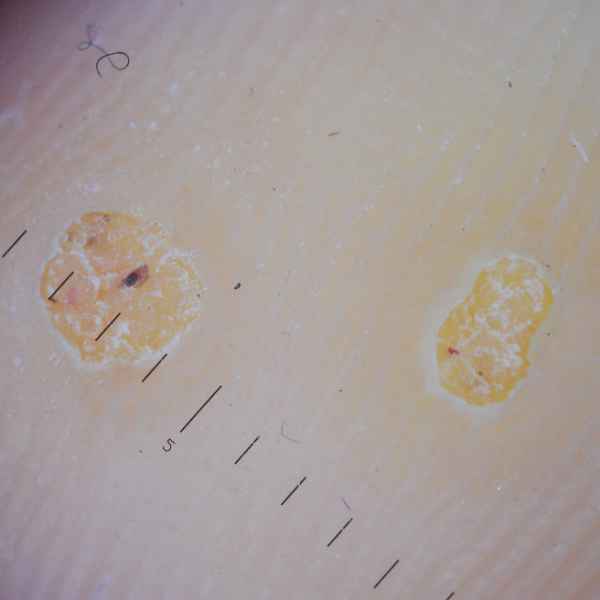

Бородавка подошвенная